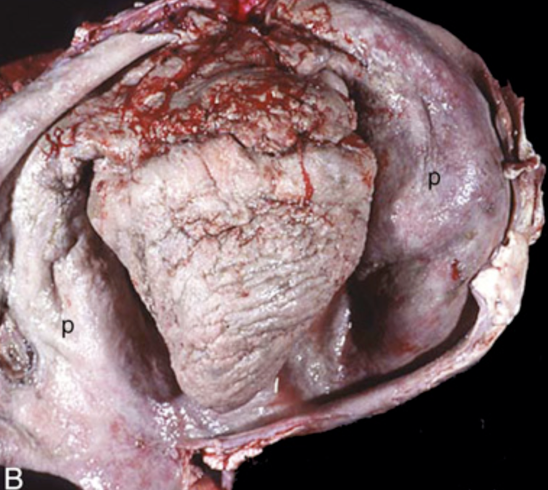

What is affecting this equine heart? note the heart is covered dorsally by a thick, yellow layer of fibrin.

fibrinous pericarditis